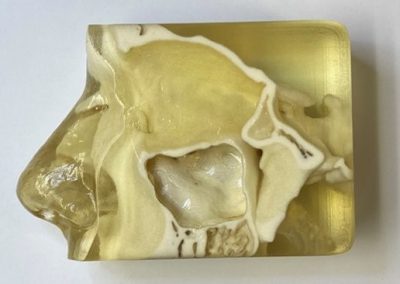

- Virtual Dissection Labs – videos of whole specimen dissections and/or interactive navigation through a whole specimen, with or without student-performed dissections of sample organs

- Plastinated specimen Lab – sample specimens infused with plastic (no movement, no interactivity, details such as nerves are poorly preserved)